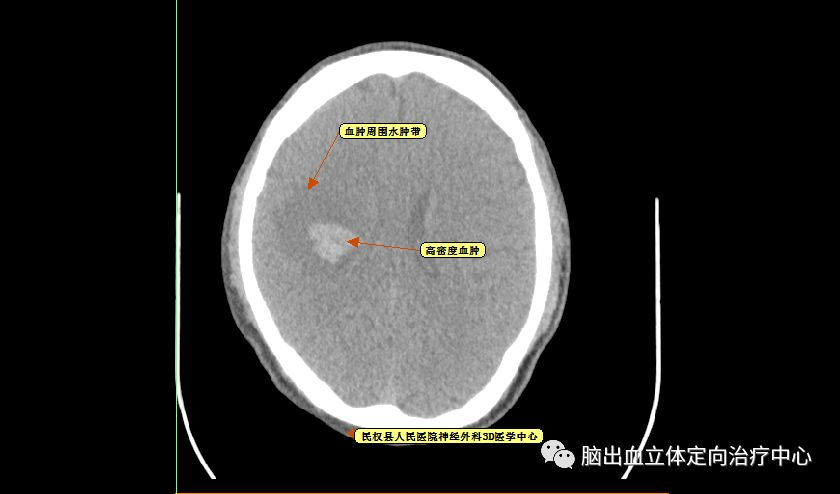

可见血肿呈分层现象,血肿周围水肿带明显,利用3D测量其各相关CT阈值。

再仔细观察并划定血肿分层区域,可设定血肿为高密度区域、低密度区域,和正常脑组织对比

以红色区域划分为高密度区域、蓝色区域划分为低密度区域